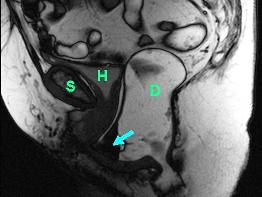

Magnetresonanz-Defäkographie

Eine andere wichtige Untersuchung stellt die Magnetresonanz-Defäkographie dar. Hierbei handelt es sich um eine funktionale Untersuchung, durch die die Bewegung des Beckenbodens während des Stuhlgangs (Defäkation) aufgezeichnet und als Filmsequenz dargestellt werden kann. Mit Hilfe dieser Untersuchung, bei der keine Belastung durch Röntgenstrahlen auftritt, können Veränderungen des Beckenbodens entdeckt werden, welche nur während des Stuhlgangs auftreten.

Die Abbildungen unten zeigen eine dynamische Untersuchung des Beckenbodens mittels Magnetresonanz-Defäkographie: Ruheposition (Abb. links) und Defäkation (Abb. rechts). Der Enddarm zeigt nach Kontrastmitteleinlauf ein helles Signal (D). Am Ende der Defäkation bildet sich eine grosse Rectocele aus (Pfeil), welche sich unter die Harnblase (H) und bis unter die Symphyse (S) schiebt. Der Enddarm kann sich aus diesem Grund nicht vollständig entleeren. Zusätzlich kommt es zu einem Tiefertreten der Harnblase (H, Abb. rechts) im Sinne einer Beckenbodenschwäche.